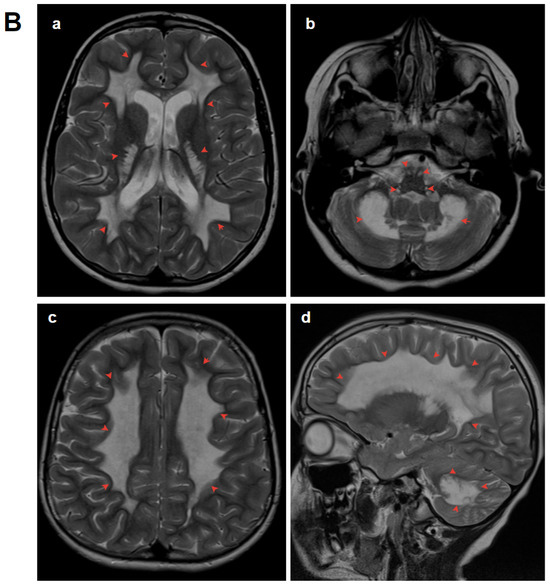

3.1.2. Patient 2